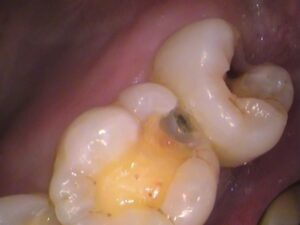

う蝕検知液で染色されないところまで丁寧に虫歯を取ります。

まだ茶色いところがありますが、

赤く染色されないので、着色であると分かります。

こちらを削ってしまうと、歯の削りすぎになります。

虫歯でないところは残しましょう。

虫歯が入っていたところは、色素が沈着し茶色く歯に色が付いてしまうことが良くあります。